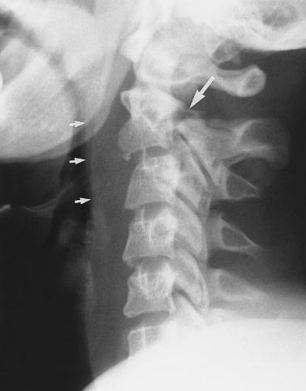

Case: A young adult attempted hanging victim with a decreased GCS was intubated and ventilated at a referring hospital. He required interhospital retrieval to a tertiary care facility. On arrival the team noted the patient was hypertensive, tachycardic and there apppeared to be patient-ventilator dysynchrony. He was sedated with midazolam only.